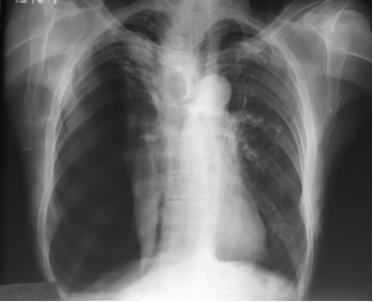

患者70岁,有慢性吸烟史和慢阻肺病史。因“呼吸困难1周”入院。临床检查:脉搏106次/分钟、血压110/78mmHg,呼吸24次/分钟,血氧饱和度90%。气管偏左,右半肺各区域无呼吸音,叩诊音高共振。实验室检查正常,除白细胞增多。胸片检查显示右侧气胸,肺塌陷,气管向左移(图1)。置入右侧ICD,气体排出,患者呼吸困难有所改善。胸片显示塌陷肺复张(图2)。

图1 胸片显示右侧气胸